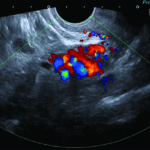

Fig. 1: Examen con Doppler color por vía transvaginal, demostrando dilatación de las venas utero ováricas del lado izquierdo.

Hallazgos imagenológicos. En el eco Doppler ginecológico por vía transvaginal se observa varicocele pelviano (Fig. 1). La vena ovárica derecha mide 3.8 mm, y la izquierda, ectásica, 7.4 mm (Fig. 2). En el eco Doppler abdominal se visualiza la vena renal izquierda, de 3.1 mm en topografía del compás aorto-mesentérico y 8.1 mm en el segmento proximal al riñón izquierdo, con una velocidad 50cm/s en el compas y 30cm/s en el segmento proximal al riñón. El estudio corresponde en primera instancia a un síndrome de Nutcracker (Fig. 3).